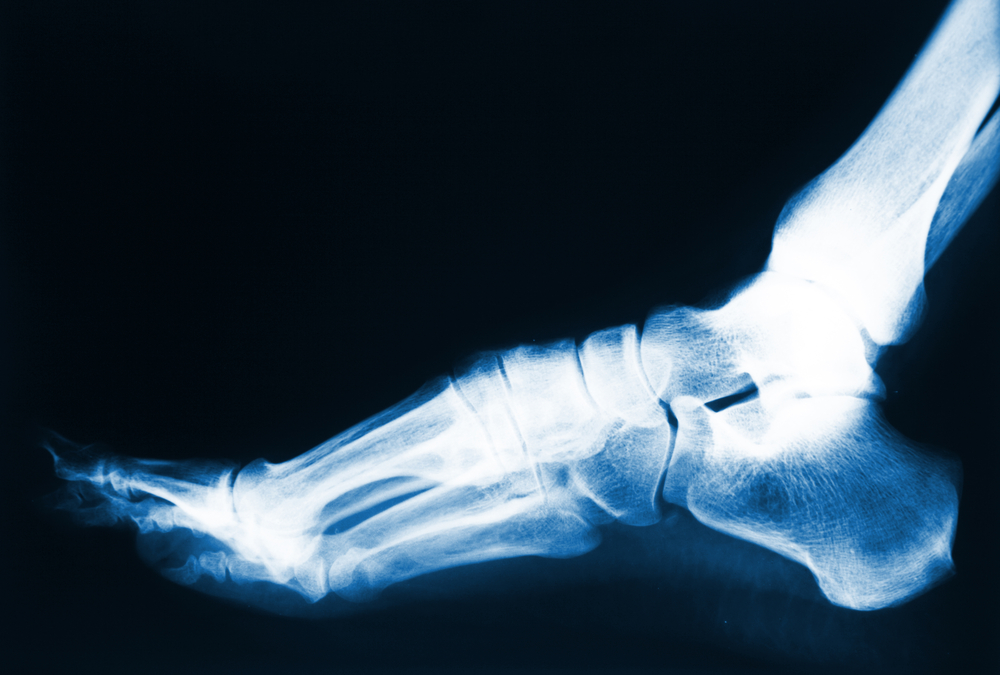

Most foot issues can be managed conservatively, and with non-invasive treatments but there are times when foot surgery might be recommended. For some patients, it might be necessary to correct an underlying issue that is causing foot pain or other problems.Reasons...